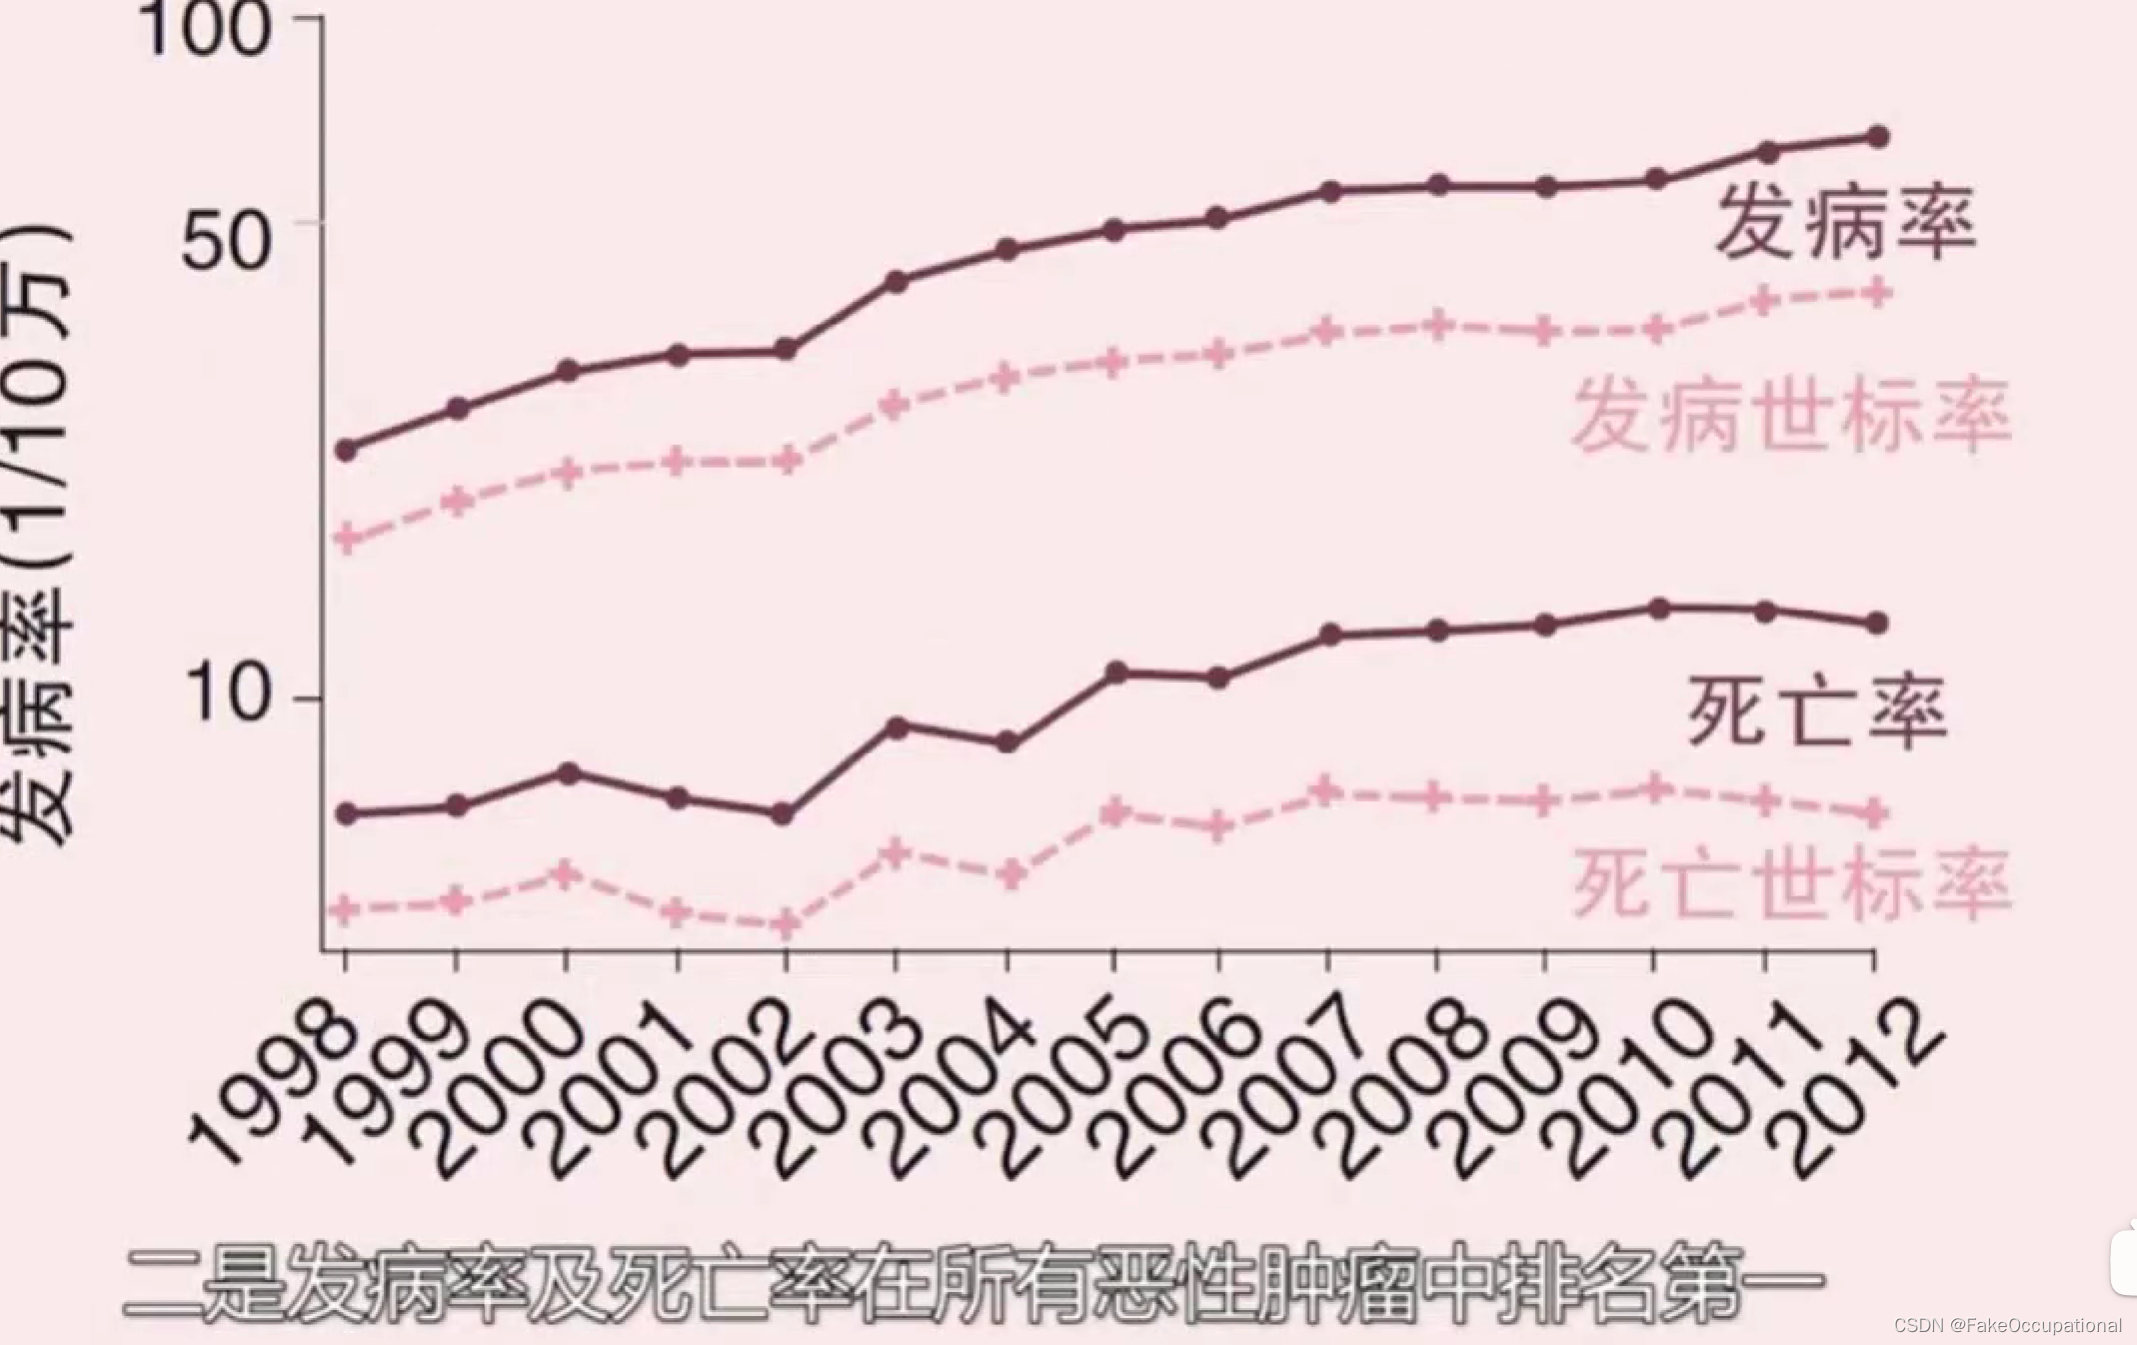

乳腺癌